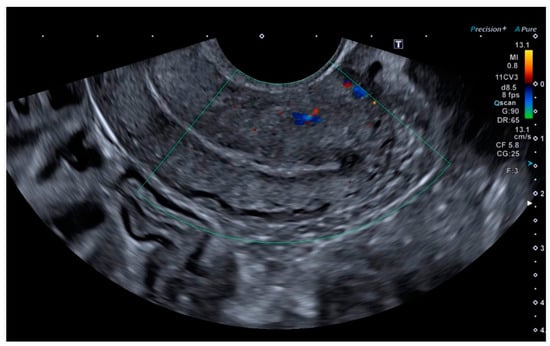

Ultrasonography showed an endometrial cavity occupied by a protruding formation in the uterine cavity measuring 38 × 15 mm, compatible with a uterine AVM (Figure 1). The presence of vascularisation of the right lateral uterine wall was noted, and pulsed Doppler showed a peak systolic velocity > 100 cm/s (Figure 2).

Figure 1. Transvaginal ultrasound with suspected uterine arteriovenous malformation.